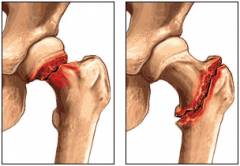

- Переломы. Важно отличать вывих бедра от перелома шейки бедренной кости или вертлужной впадины. В некоторых случаях может быть только перелом, а в других – он может сочетаться с вывихом, образуя переломовывих.

- Невозможность закрытого вправления. Это может быть связано с капсулой сустава или другими тканями, застрявшими между головкой бедра и вертлужной впадиной.

Во время операции хирург делает разрез для доступа к суставу, устраняет повреждения (удаляет ткани, попавшие в сустав, и восстанавливает разорванные связки), выполняет открытое вправление головки бедра и накладывает швы.

- Открытое вправление вывиха. Применяется, если суставные поверхности целы.